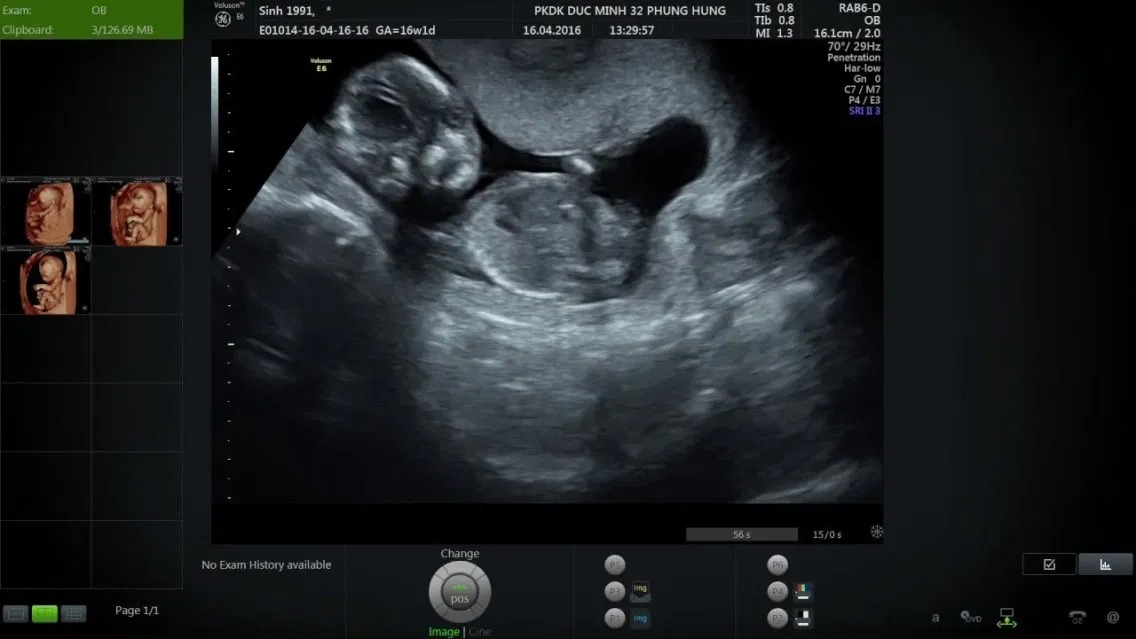

Qua hình ảnh siêu âm, mẹ bầu có thể nhận thấy có thêm cả sự thay đổi ở kích thước thai 16 tuần. Ở các tuần trước, phần đầu thường to hơn phần thân nhưng sang đến tuần này, kích thước phần đầu so với thân đã dần cân đối hơn. Đốt sống cổ dần hình thành và phát triển, hỗ trợ phần đầu thai được nâng lên cao hơn.

Khi theo dõi kết quả siêu âm, bác sĩ sẽ cho người mẹ biết được giới tính thai nhi. Như vậy, có thể nói, việc xác định thai nhi tuần thứ 16 là trai hay gái là hoàn toàn có thể. Tuy nhiên, trong một vài trường hợp, hình ảnh siêu âm không hiện lên bộ phận sinh dục của bé do tư thế nằm không thuận lợi. Tỷ lệ này chỉ khoảng dưới 20%.

Hình ảnh siêu âm thai nhi 16 tuần tuổi hiện nay đã được cải tiến với chất lượng tốt hơn, có thể cung cấp cho mẹ biết những thông tin sau.

Bước sang tuần thai thứ 16, bộ phận sinh dục của bé đã hình thành đầy đủ. Với công nghệ siêu âm 4D và sự hỗ trợ của bác sĩ, ba mẹ có thể quan sát bộ phận này trên hình ảnh siêu âm.